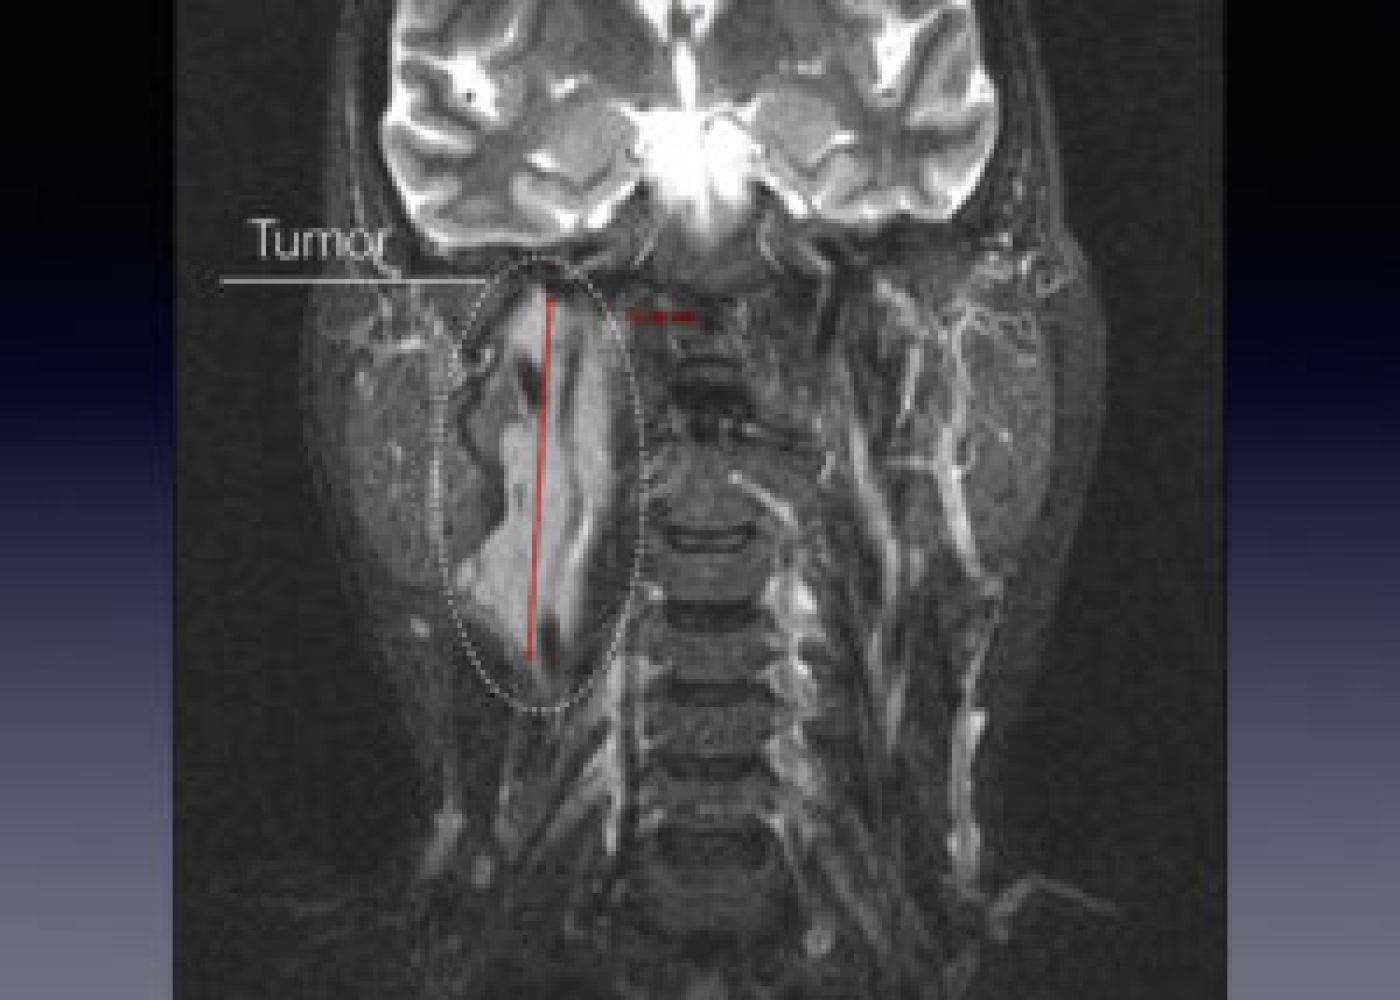

Պացիենտի խոսքով՝ գանգատներն ի հայտ են եկել մոտ 1,5 տարի առաջ և հաջորդիվ գոյացության չափերը զգալի մեծացել են: Հետազոտման ժամանակ աջից պարանոցի քնային եռանկյունում հայտնաբերվել է հստակ սահմաններով մոտ 4սմ տրամագծով անցավ գոյացություն:

Կլինիկոպարակլինիկական հետազոտությունների արդյունքում ախտորոշվել է քնային զարկերակի բիֆուրկացիայի անգիոմիոմատոզ համարտոմա աջից, որը ճնշում էր արտաքին քնային զարկերակը: